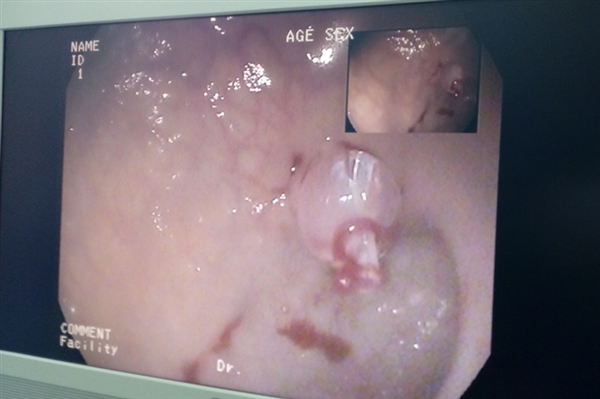

6月11日,我院成功为一位93岁高龄的患者实施了经皮内镜下胃造瘘术。

经医院老年科、胃肠镜室、麻醉科综合评估后,决定为患者行经皮内镜下胃造瘘术解决进食问题,保证营养支持。术中,胃肠镜室与麻醉科通力协作,局部麻醉、定位穿刺点、套管穿刺......在医务人员们的精准操作下,仅用了半小时就顺利为患者完成了PEG,术后无不良反应。

据悉,术后24小时,毕大爷就可以通过造瘘管进食了,保证了营养支持,提高了生活质量,对疾病的恢复具有积极作用。